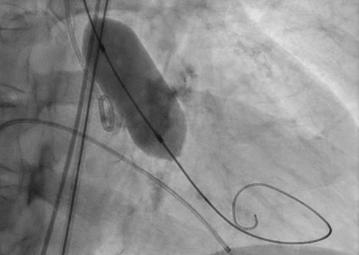

Navigator with Myval THVNavigator balloon with dual expansion ports at each end ensures rapid, simultaneous, controlled expansion (dog-boning) of distal and proximal ends

This typical dog bone pattern of inflation steadies the valve during expansion phase, ensuring its precise annular position and deployment without any risk of valve migration

Rapid balloon inflation, using an inflation device is possible with controlled palm thrust

Rapid balloon deflation within 3-5 sec ensures procedural safety and compliance